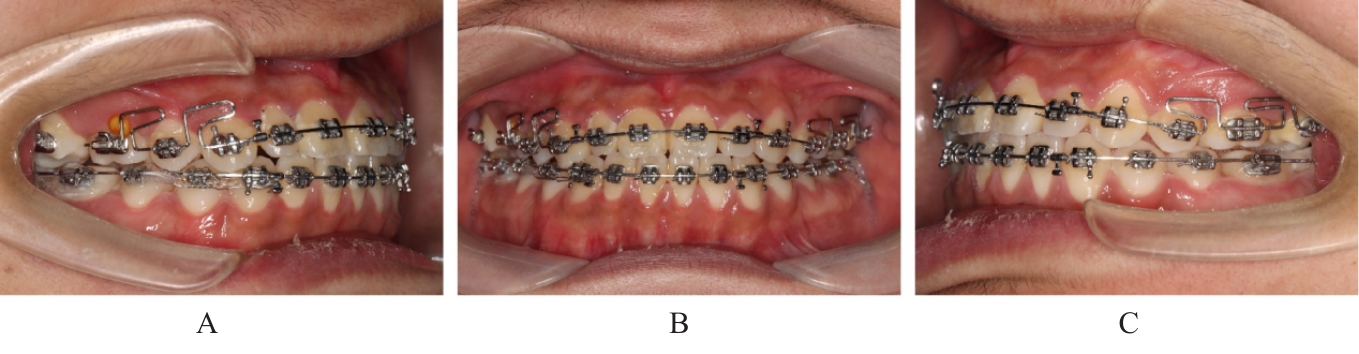

Grade Ⅲ open bite complicated with tongue hypertrophy treated by mandibular incisor extraction:A case report and literature review

Lei TIAN,Yuyan LIU,Yuqing WANG,Zhiyu ZHANG,Xiumei SUN( )

- Department of Orthodontics,Stomatology Hospital,Jilin University,Changchun 130021,China